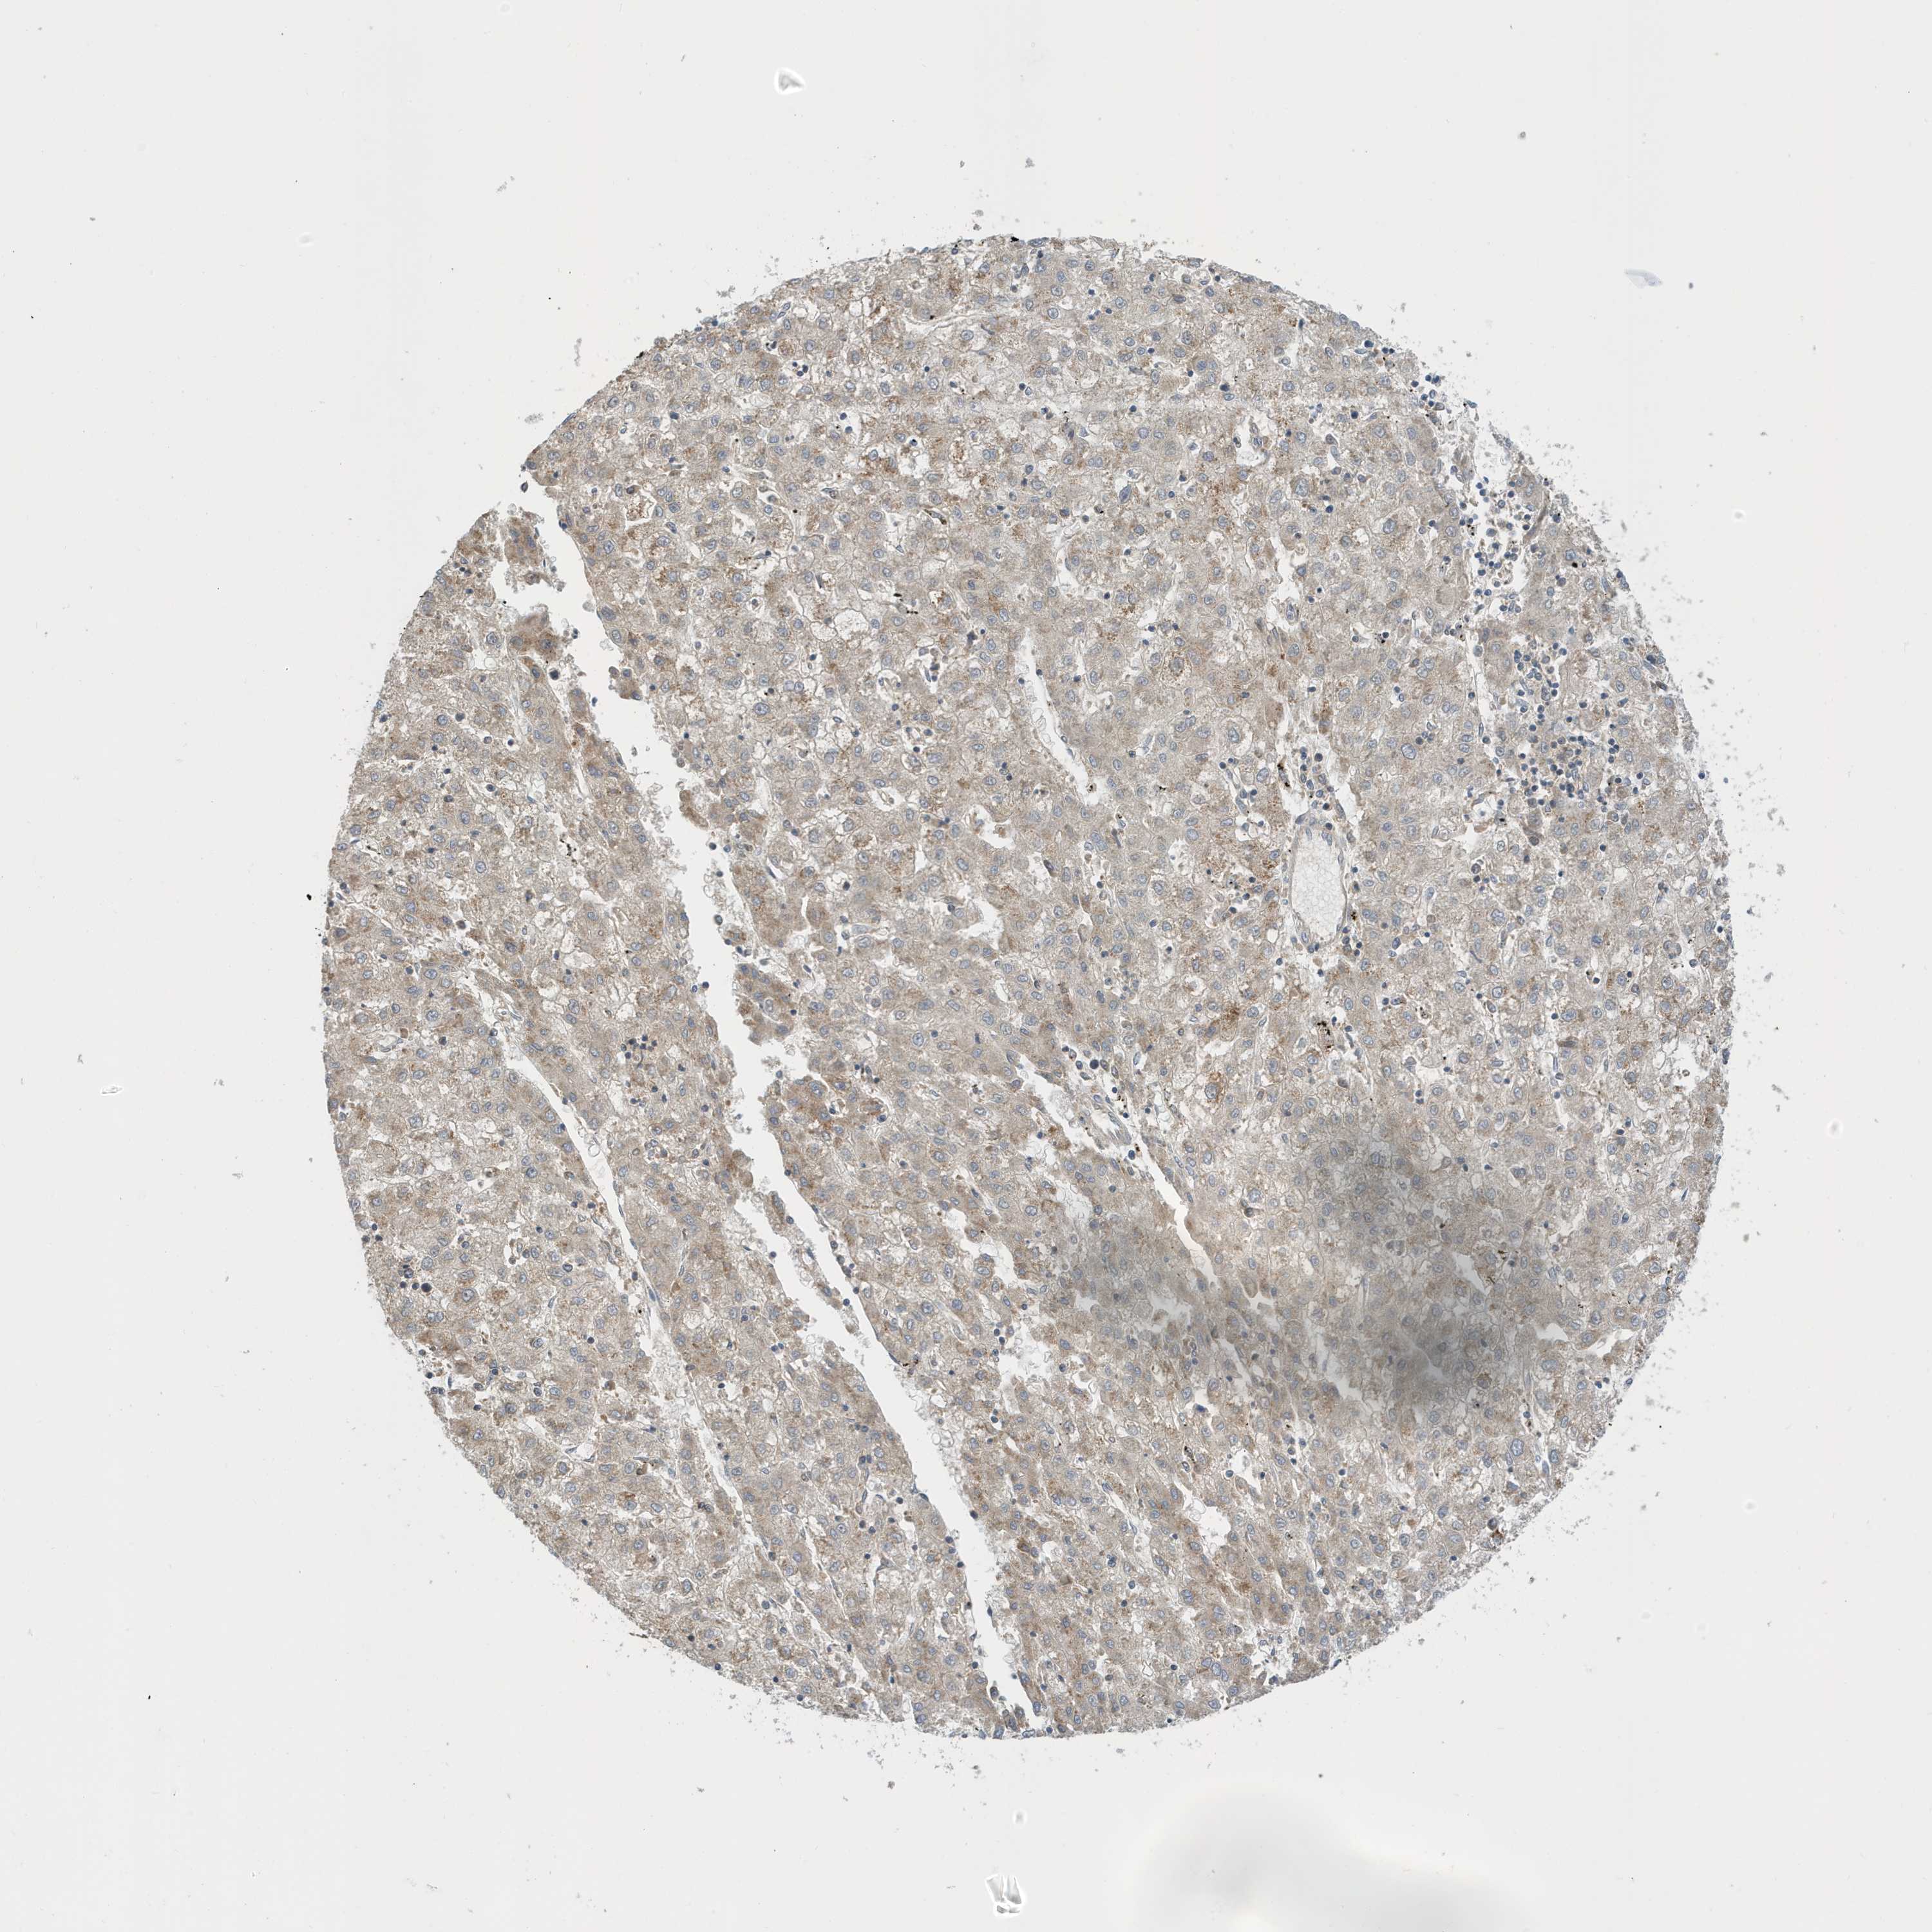

LIVER CANCER - Protein expressioni

A mouse-over function shows sample information and annotation data. Click on an image to view it in a full screen mode. Samples can be filtered based on level of antibody staining by selecting one or several of the following categories: high, medium, low and not detected. The assay and annotation is described here.

Note that samples used for immunohistochemistry by the Human Protein Atlas do not correspond to samples in the TCGA dataset.

Antibody stainingi

Antibody staining in the annotated cell types in the current human tissue is reported as not detected, low, medium, or high, based on conventional immunohistochemistry profiling in selected tissues. This score is based on the combination of the staining intensity and fraction of stained cells.

Each image is clickable and will lead to virtual microscopy that enables deeper exploration of all samples and also displays staining intensity scores, fraction scores and subcellular localization as well as patient and tissue information for each sample.

Antibody HPA036181

Staining

High

Medium

Low

Not detected

Intensity

Strong

Moderate

Weak

Negative

Quantity

>75%

75%-25%

<25%

None

Location

Nuclear

Cytoplasmic/membranous

Cytoplasmic/membranous,nuclear

Cholangiocarcinoma

Carcinoma, Hepatocellular, NOS